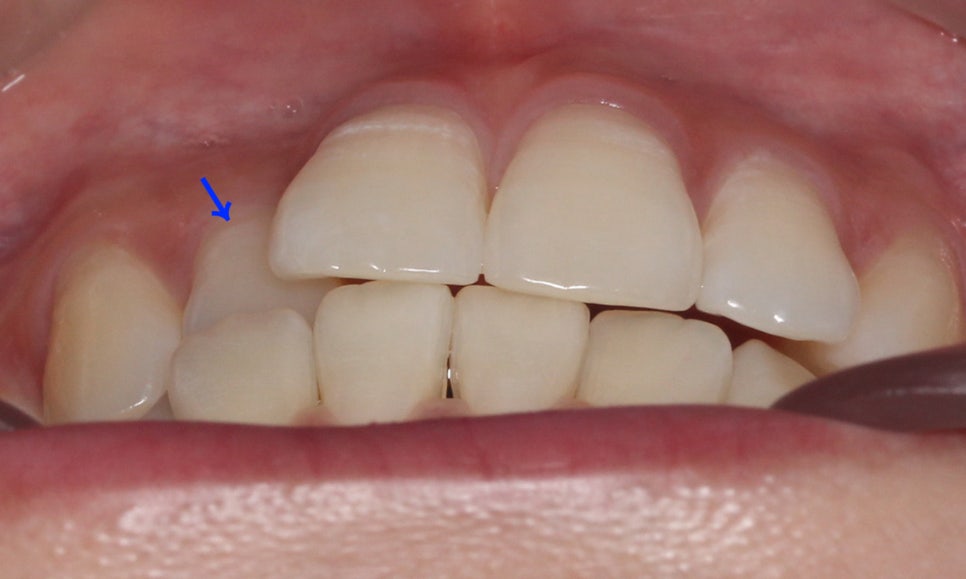

overbite 사진을 보면 상악 좌측 측절치가

하악보다 뒤쪽으로 교합되는 모습을

확인할 수 있는데요, 이렇듯 일부 치아에

반대교합 증상이 나타날 경우 2D교정이나

투명교정을 통해 단기간에 심미적인

치아 교정이 가능합니다.

전치부의 돌출 정도를 확인할 수 있는

overjet 수치는 비교적 돌출감이 없는 모습으로

거꾸로 물리는 측절치를 해결한다면

스마일라인의 심미성을 보완할 수 있을 것으로 보입니다.